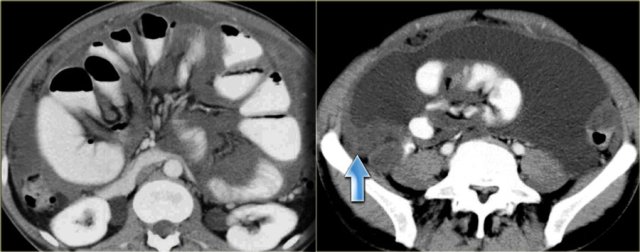

Pseudomyxoma peritonei (2)

On the left another case of pseudomyxoma peritonei.

There is hardly any scalloping of the liver.

Notice the thickened falciform ligament.

There is a mucocele of the appendix (arrow).

This finding is only rarely seen.

There is compression of the mesentery resulting in a thickened cake-like hyperdense mesentery (arrow).

There are also some calcifications.